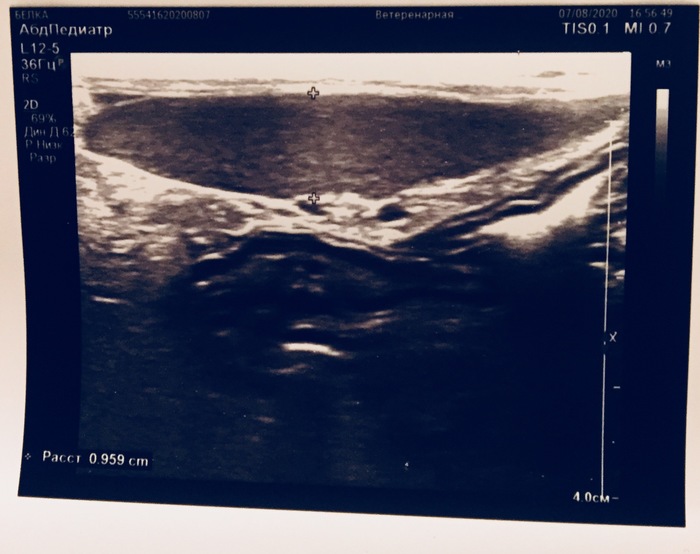

Продолжение поста «Заболела наша Белка, подобранная на улице. Жидкость в брюшной полости и гематома печени. Завтра вечером будут готовы анализы»1

Всем привет от Белки. Пришли анализы крови. Все более менее. Анализы нетипичны для ФИП. Очень надеемся, что это печень. Если это так, то потребуется срочная операция по удалению гематомы. Но это лечится довольно успешно и кошки с этим живут. Сейчас я капаю Белку дома. Приходится изобретать способы для подвешивания бутылки с раствором. Завтра будет готов анализ жидкости. Сейчас у неё опять температура 39.8. Скорее всего, будем давать жаропонижающее. Белка ест и пьёт сама.

Заболела наша Белка, подобранная на улице. Жидкость в брюшной полости и гематома печени. Завтра вечером будут готовы анализы1

Всем привет. Несколько дней назад Белке стало плохо - поднялась температура. Она стала тяжело дышать. Стала хуже есть. Сидеть в напряжённой позе.

Сегодня @LazyMouse26 повезла Белку в клинику на обследование. Сделали УЗИ, рентген, откачали жидкость из живота (100 мл). Увидели небольшое количество жидкости в легких. Жидкость отправили на два анализа - ФИП и на бактерии. Завтра вечером будет готов результат.

На части печени ясно видна гематома.

Каков результат? У нас два варианта, один из которых ФИП, другой - гематома.

Мы очень надеемся, что это гематома. Ее можно будет удалить и Белка поправится.